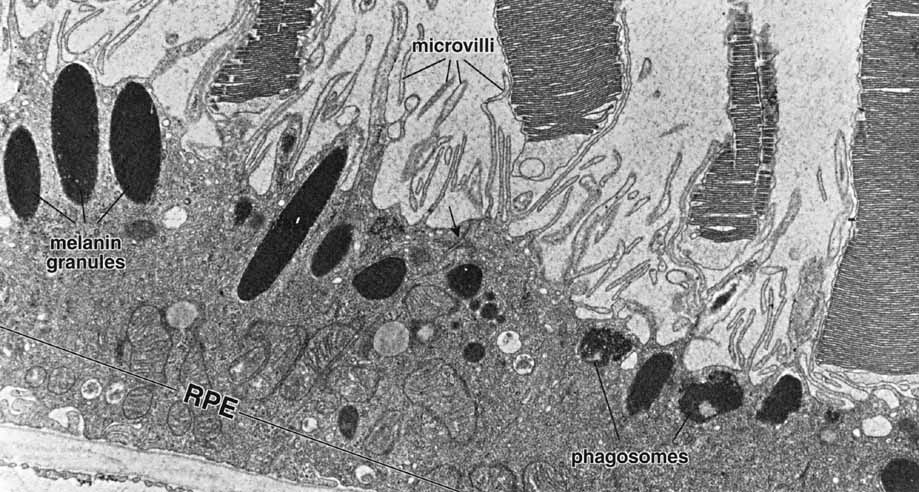

Fig. 4 Electron micrograph of the retinal pigment epithelium in association with the outer segments of rods and cones. Retinal pigment epithelium (RPE) contains numerous elongated melanin granules that are aggregated in the apical portion of the cell, where the microvilli extend from the surface toward the outer segments of the rod and cone cells. The retina pigment epithelial cells contain numerous mitochondria and phagosomes. The arrow indicates the location of the junction complex between two adjacent cells, ×20,000. (Courtesy of Dr. Toichiro Kuwabara and reproduced from Ross et al. 2003)

As already discussed, the topography of retinal development results in the intimate association of RPE apical microvilli with rod and cone photoreceptor outer segments across the intraretinal space (Figs. 4 and 6). These are bound together by the interphotoreceptor matrix (IPM), a network of proteins and proteoglycans containing a variety of enzymes, growth factors, carrier proteins, and other constituents.4 A number of constituents of this matrix have been localized in three distinct patterns, such as those that demonstrate rod- and cone-specific localization, those with an apical-to-basal heterogeneity, and others with a more homogeneous distribution. When there is a neurosensory retinal detachment, the potential interphotoreceptor space expands as fluid accumulates to form what is clinically referred to as the subretinal space, and the photoreceptors, now deprived of their supportive RPE functions, will degenerate if re-attachment is not effective. To maintain normal retinal attachment, RPE cells develop long slender apical microvilli of 5 to 7μm in length, forming sheaths that appear to participate in phagocytosis of outer segments. Villous processes surrounding rods contain smooth endoplasmic reticulum, ribosomes, melanin granules, and actin filaments. Villous processes that surround extrafoveal cones are usually devoid of intracellular organelles except for pigment granules. Despite their intimate relationship, no junctional attachments have been found between the RPE apical processes and the photoreceptor outer segments, although several molecular mechanisms forming the basis of this recognition and adhesion have been proposed, as discussed later.

THE RPE AND PHOTORECEPTOR OUTER SEGMENT PHAGOCYTOSIS

RPE cells play a critical role in the process of turnover and renewal of shed photoreceptor outer segments (Figs. 14 and 15). The amount of material processed by the RPE is quite prodigious, and classic experiments identified both the diurnal nature of the process, and estimated that the total amount of photoreceptor membrane material processed per day may be as much as four times the surface area of the RPE cell membrane itself.55–57 The phagocytic process occurs through engulfment by the apical membrane of the RPE, and although the RPE is capable of slow, nonspecific phagocytosis of a diversity of large and small particles, it is the daily, specific phagocytosis of photoreceptor outer segment disks that constitutes one of the most important functions of RPE cells.58 If the phagocytic capacity of the RPE is impaired, the photoreceptor cells are unable to renew the outer segments, and as a consequence the photoreceptors degenerate and die. Once a phagosome has formed following internalization, fusion occurs with lysosomes, and if lysosomal proteases are inhibited, the RPE rapidly becomes engorged with undegraded phagosomes.59 The phagocytic load, that is, the number of photoreceptor disks shed per day per RPE cell, was calculated by Young to be 2000 disks per day in the parafovea, 3500 in the perifovea, and nearly 4000 in the periphery of the monkey eye. Phagocytosis by the RPE results in the complete turnover of the photoreceptor outer segments once every 8 to 13 days.60 Although the specific receptors of the apical RPE membrane involved in this process remain to be definitively identified, a variety of cell-surface proteins have been experimentally implicated in recognition, binding, and endocytosis of photoreceptor outer segments by RPE cells, including receptors for glycoproteins containing high levels of the sugar mannose,61 and cell surface receptors such as CD36 and the specific integrin alpha(v)beta5.62,63